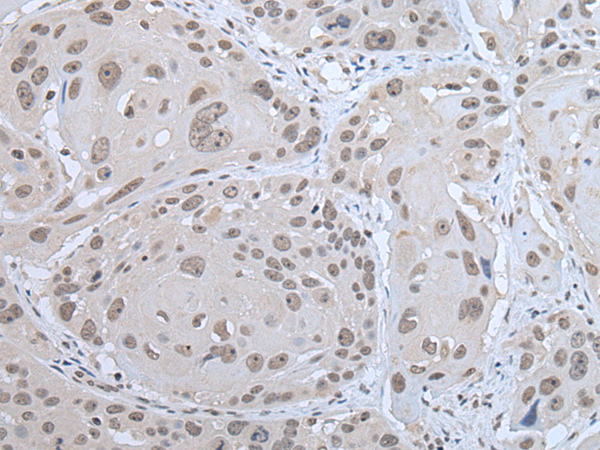

分类: 科研抗体货号: P12735别名: FOV; CA11; AMP18; BRICD1; foveolin应用: WB,IHC反应种属: Human

分类: 科研抗体货号: P12743别名: HOX3; HOX3B应用: WB,IHC反应种属: Human, Mouse